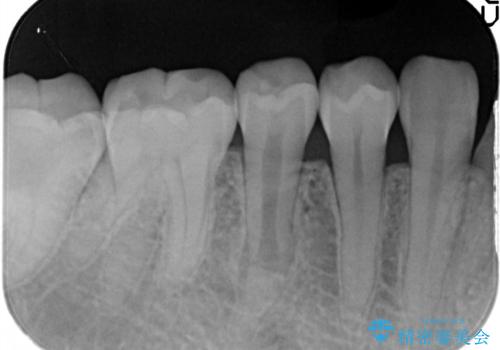

【根管治療】噛んだ時にしみる。最近になってズキズキ痛み、長引く痛みがある

担当医 河口智英